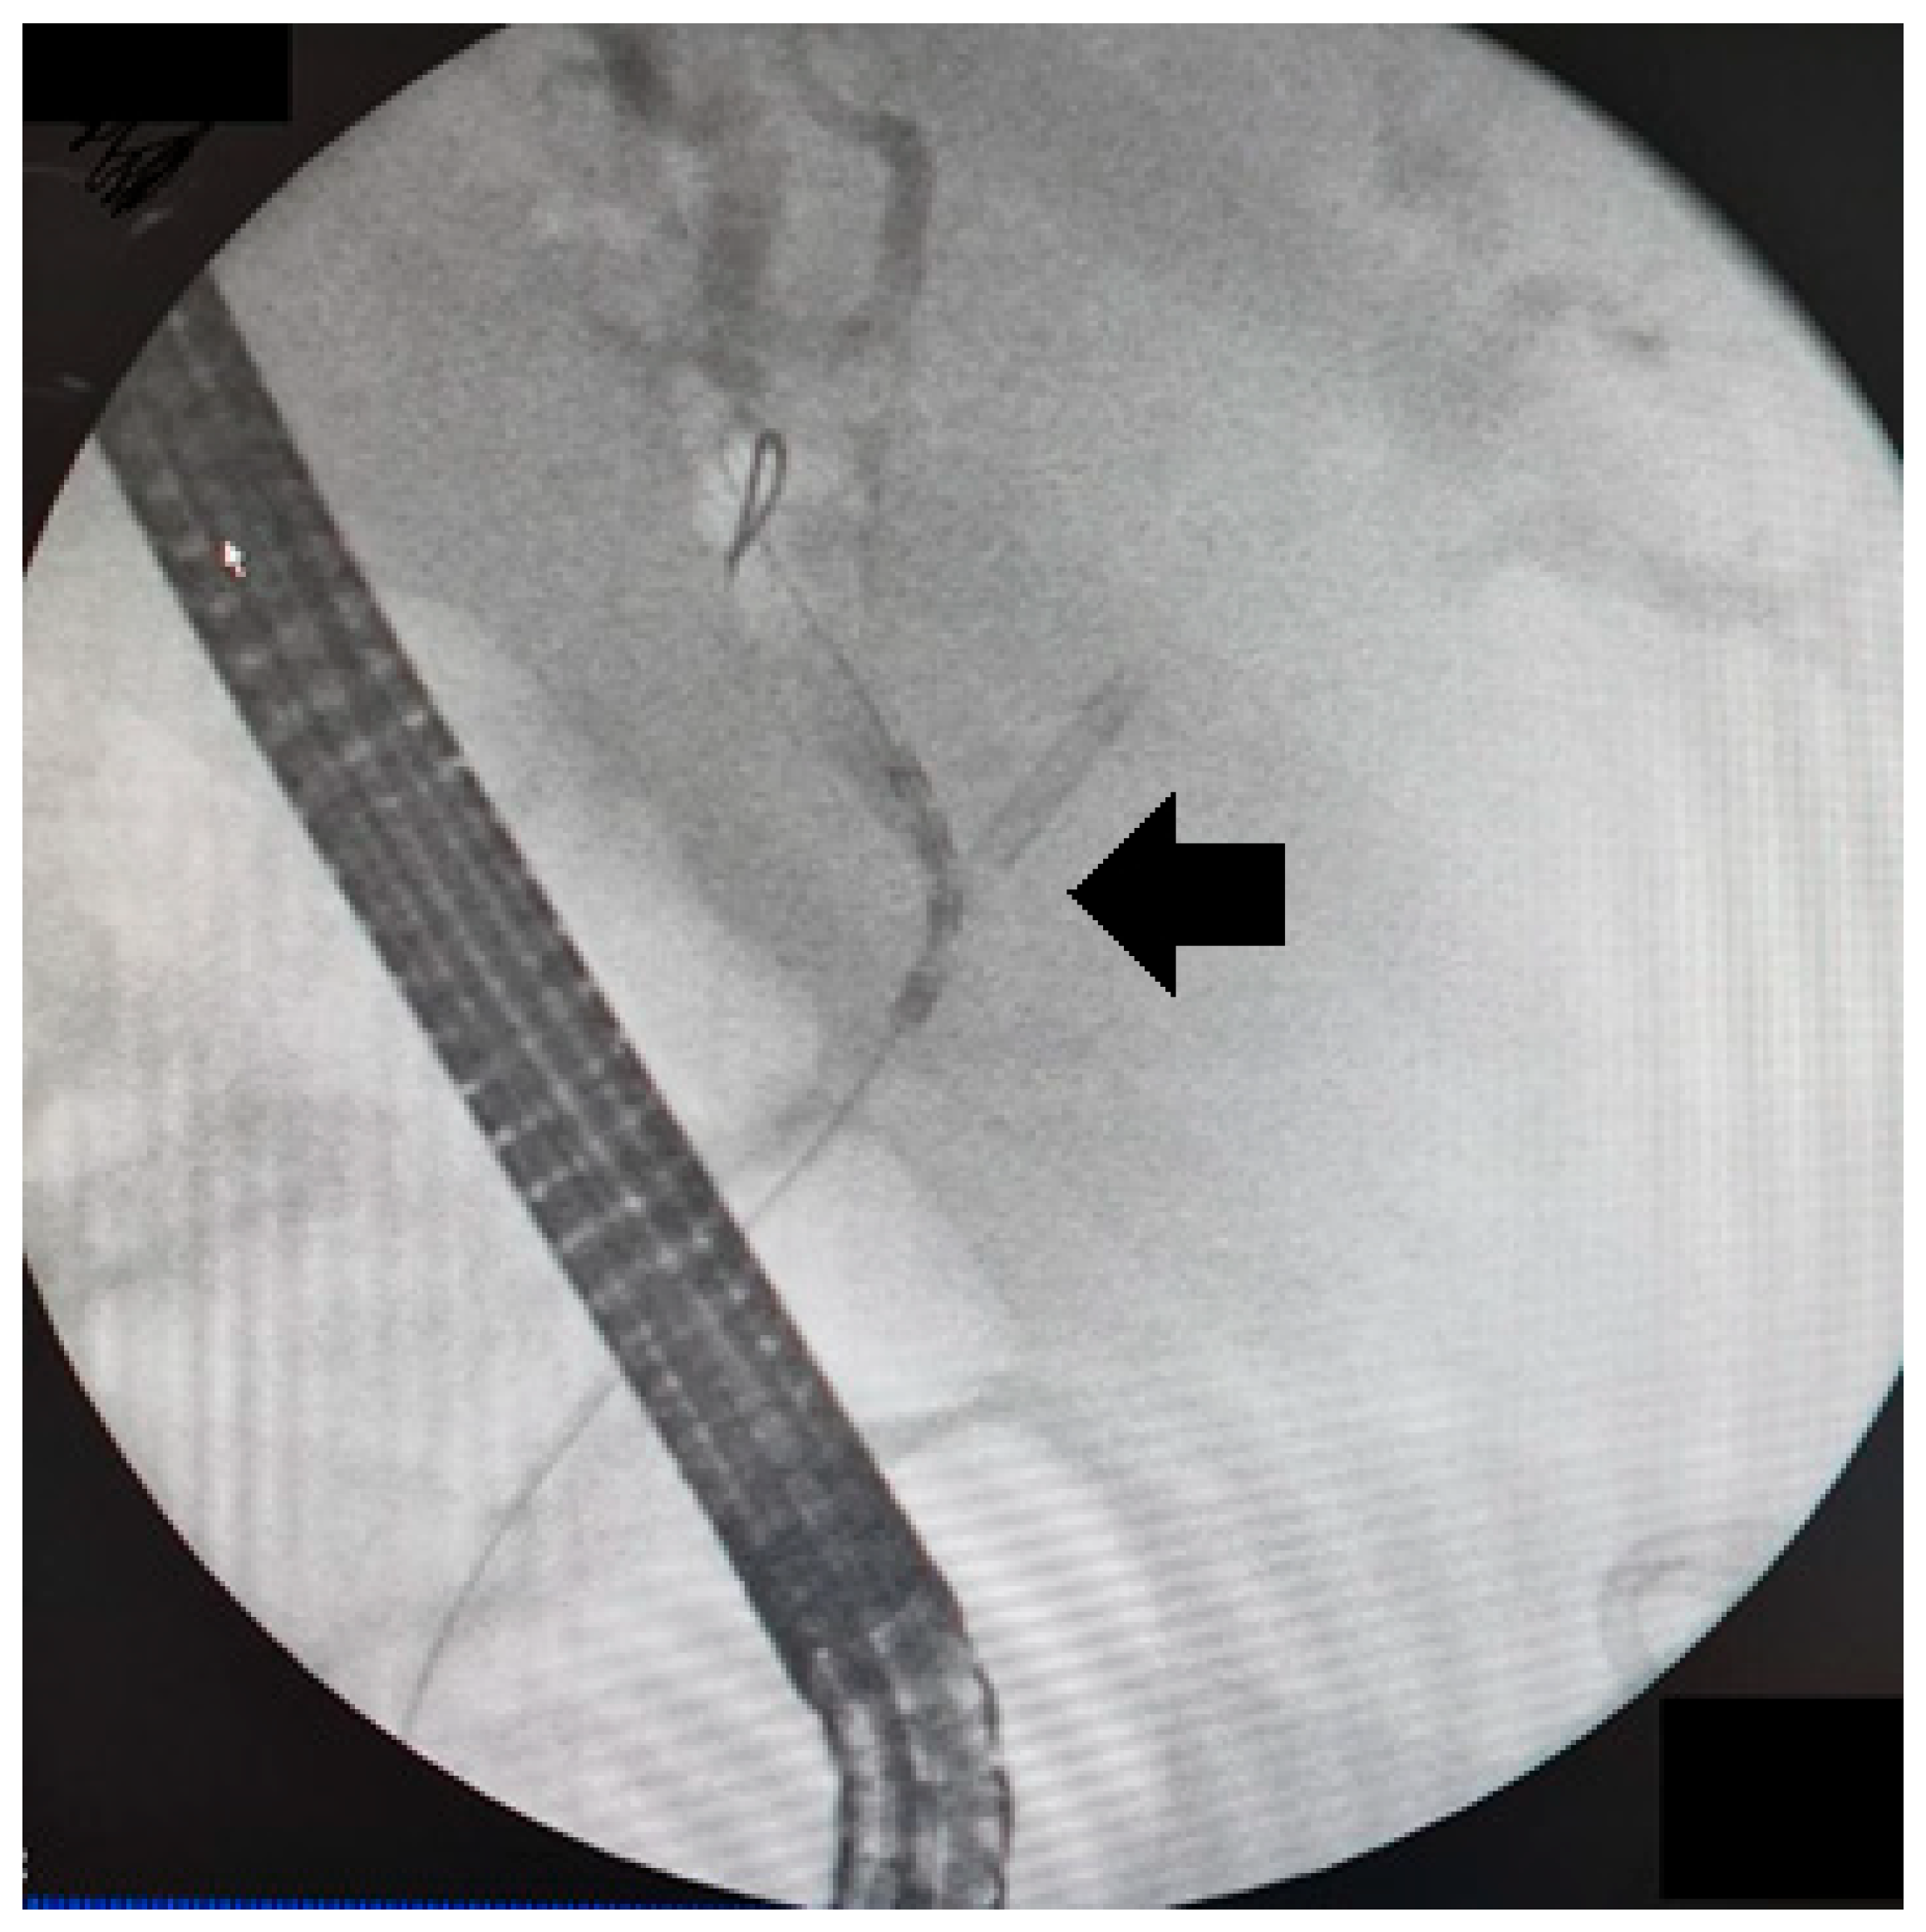

Figure 2. Endoluminal RFA catheter (StarMed ELRA) positioned across the biliary stricture during ERCP. The location of the malignant stricture/target ablation segment is indicated by an arrow on the fluoroscopic image.